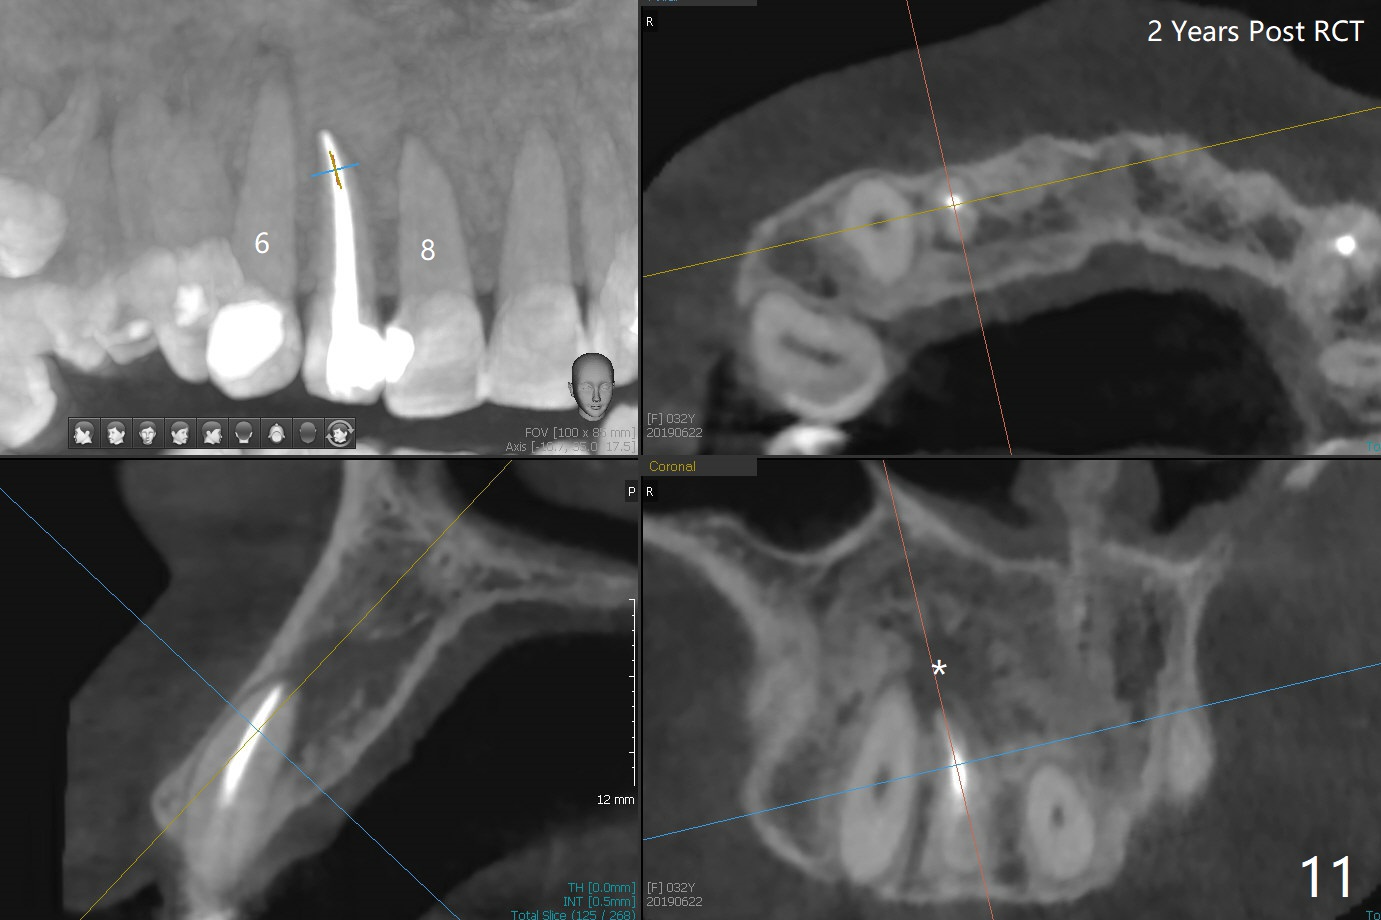

A 30-year-old woman presents to clinic with a large palatal swelling (Fig.1,2). In fact the tooth #7 is necrotic with a periapical radiolucency (Fig.2 arrowheads). RCT is initiated; note the curved canal and file (Fig.3). To reduce the large lesion, Calcium Hydroxide paste is placed in the enlarged canal (Fig.4 *). In a month, the palatal lesion decreases (Fig.5). After re-debridement of the canal, Calcium Hydroxide paste is re-applied.

When this patient returns with improvement of symptoms, RCT will be finished. In fact the swelling relapses a month later (Fig.6). After discussion of possible cyst enucleation and increase in debridement from 30/.04 to 40/.06, a master cone of 40/.06 is inserted (Fig.7) and RCT is finished (Fig.8). Although the patient reports relapse of swelling, the palate looks normal and bone density increases 7 months postop (Fig.9). For 14 implant placement, CT is taken 2 years 1 month post RCT (Fig.10,11). Radiolucency is confined to the apex of the tooth #7 (white *). The labial concavities mesial and distal to the left lateral incisor makes radiolucencies (bone loss) look more radiolucent, creating globumaxillary cyst image. The globumaxillary cyst is a terminology for its shape. It does not mean congenital in nature. The treatment is dependent upon vitality test of the involved teeth.